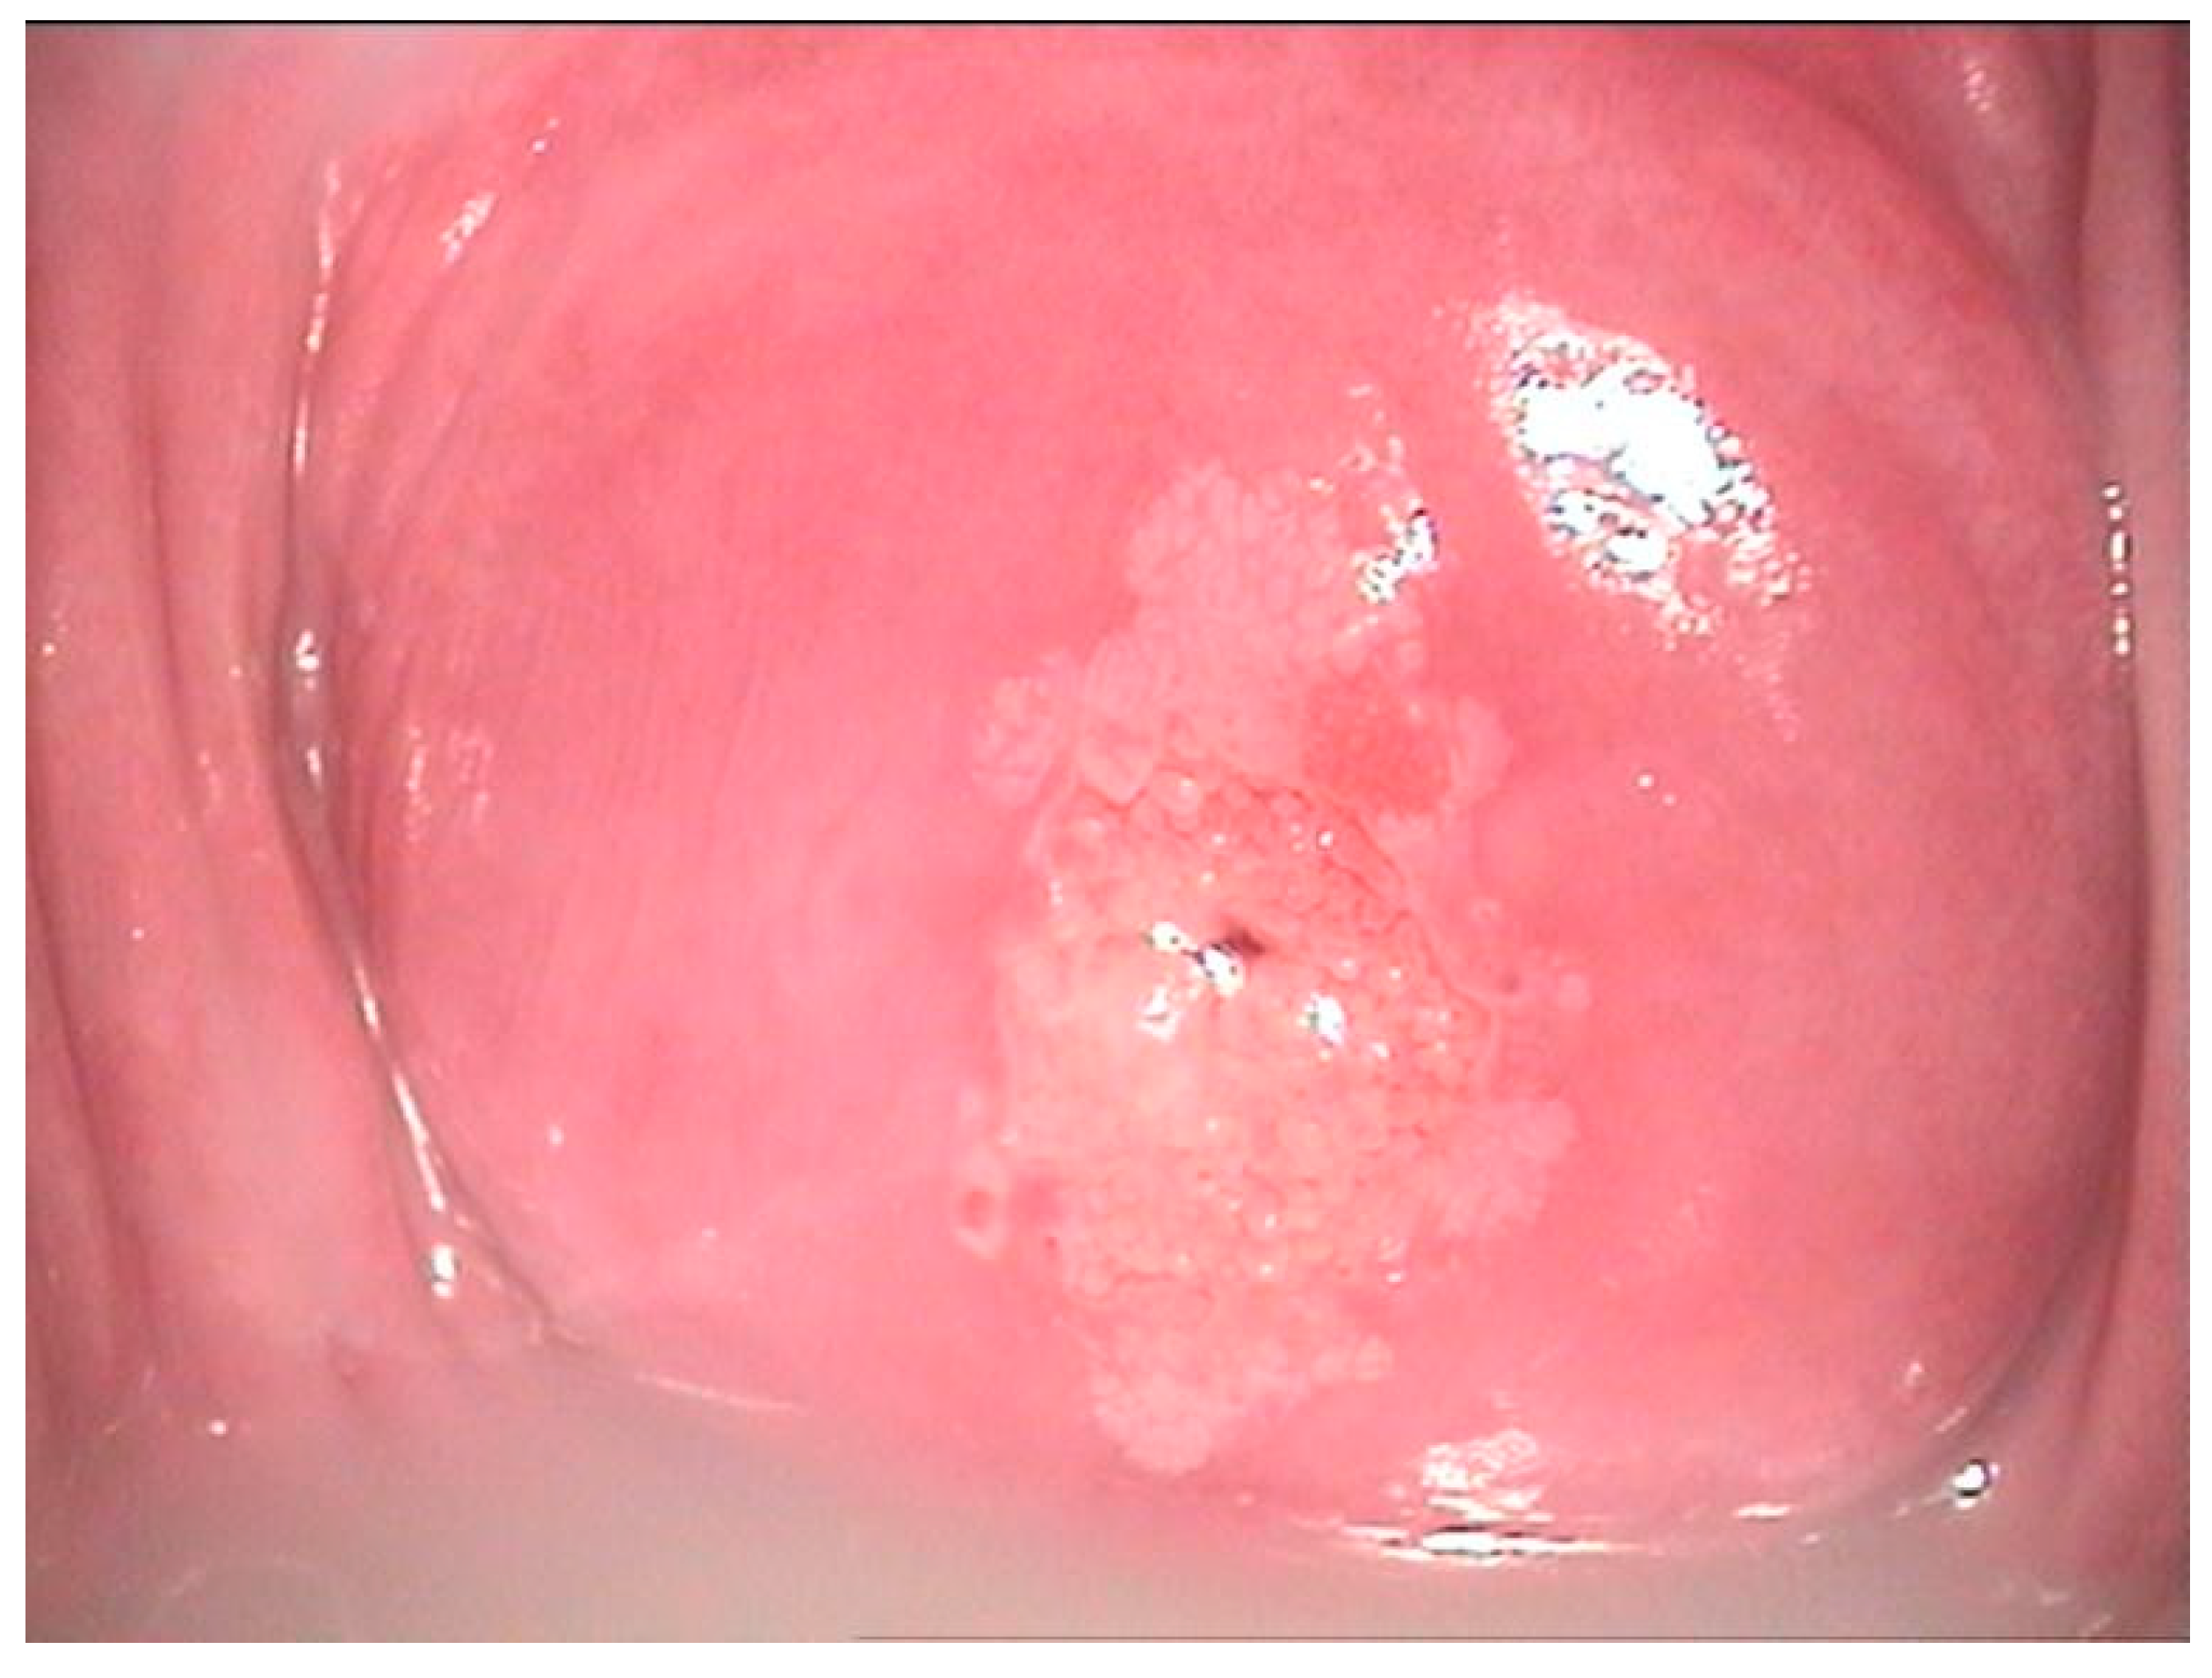

2.2. Clinical Examination